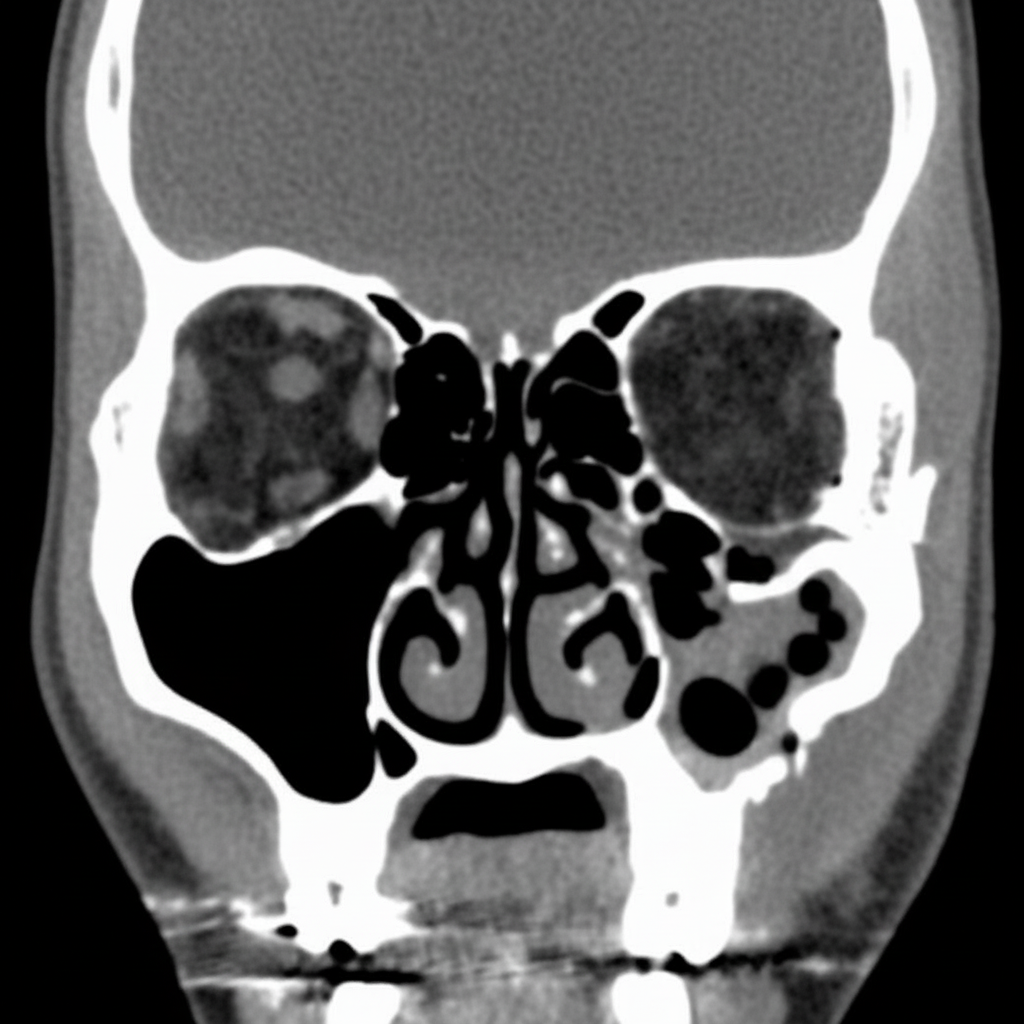

Based upon this coronal CT view of the face in a 25-year-old man with eye pain, what is the MOST likely diagnosis?

Explanation: ***Blowout fracture*** - Classic coronal CT findings include the **teardrop sign** (herniated orbital fat into maxillary sinus) and **orbital floor disruption** with associated eye pain. - Typically occurs after **blunt trauma** to the orbit, causing increased intraorbital pressure and fracture of the thin orbital floor. *Maxillary sinusitis* - Would show **mucosal thickening** or **fluid levels** within the maxillary sinus, not orbital fat herniation. - Presents with **facial pain** and **nasal congestion** rather than isolated eye pain from orbital injury. *Neoplasm of the maxillary sinus* - Appears as a **soft tissue mass** with possible **bone destruction** and irregular margins on CT. - Typically presents with **chronic symptoms** like nasal obstruction and epistaxis, not acute eye pain in a young patient. *Orbital lipoma* - Shows as a **well-defined fatty mass** within the orbit with **homogeneous fat density** on CT. - Does not cause **orbital floor fracture** or herniation into the maxillary sinus, and is usually asymptomatic.

Explanation: **Explanation:** The **"Tear Drop Sign"** is a classic radiological finding in **Orbital Floor Fractures** (specifically Blow-out fractures). It refers to a soft tissue mass hanging from the roof of the maxillary sinus on a Water’s view (occipitomental projection) or CT scan. This "teardrop" appearance is caused by the herniation of orbital fat and the **inferior rectus muscle** through the fractured orbital floor into the maxillary sinus. **Why the other options are incorrect:** * **Zygomatic bone fracture:** Typically presents with the "Tripod fracture" pattern (involving the zygomatic arch, inferior orbital rim, and zygomaticomaxillary buttress). It does not produce a localized teardrop herniation. * **Mandibular fracture:** These are usually diagnosed by identifying cortical breaks or displacement on an OPG (Orthopantomogram). Clinical signs include malocclusion and "step-off" deformities. * **Hyoid bone fracture:** A rare injury often associated with strangulation or direct neck trauma; it is diagnosed by lateral neck X-rays showing bone discontinuity, not sinus herniation. **High-Yield Clinical Pearls for NEET-PG:** * **Mechanism:** Blunt trauma to the eye (e.g., a cricket ball or fist) increases intraorbital pressure, causing the thin orbital floor (maxillary bone) to "blow out." * **Clinical Sign:** Patients often present with **diplopia** (double vision) on upward gaze due to entrapment of the inferior rectus muscle and **enophthalmos** (sunken eye). * **Associated Nerve:** The **infraorbital nerve** is frequently involved, leading to anesthesia or paresthesia of the cheek and upper lip. * **Black Eyebrow Sign:** Another radiological sign of orbital fracture representing intraorbital emphysema (air from the sinuses entering the orbit).